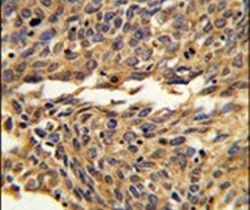

- Immunohistochemical analysis of formalin-fixed, paraffin-embedded human lung carcinoma tissue using an EXOC5 polyclonal antibody (Product # PA5-26024), followed by HRP-conjugated secondary antibody and DAB staining.